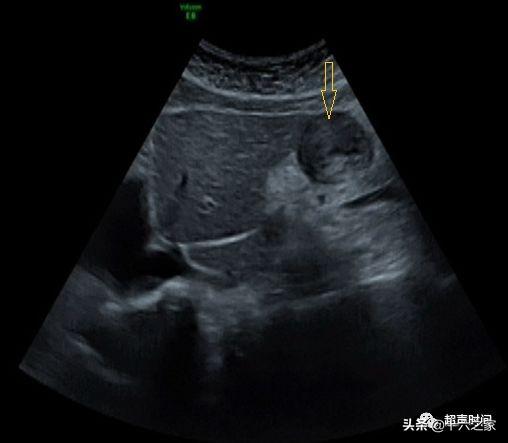

超声检查图像:胃窦切面 黄箭头指向病灶胃声学造影诊断思路分析:该